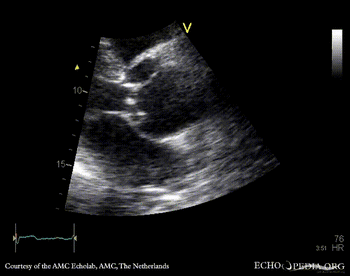

Aortic dissection type A

A3CH A3CH with Color Doppler: mild aortic regurgitation